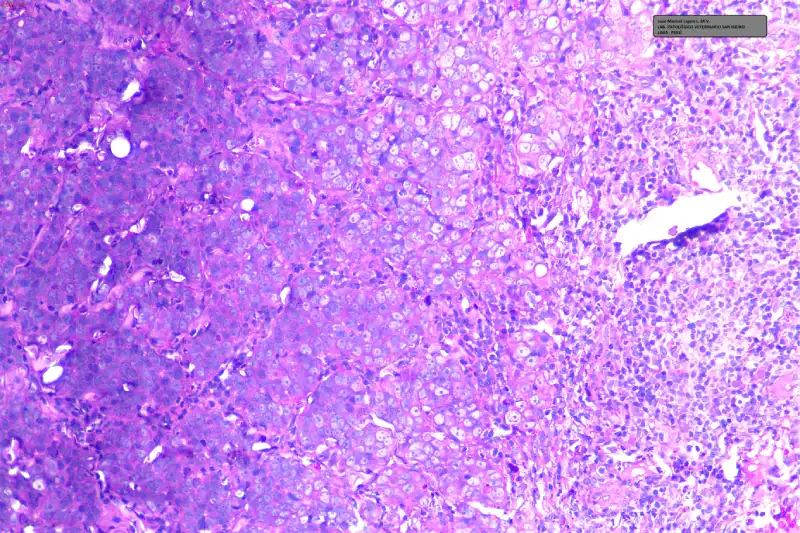

Las muestras para estudio histopatológico fueron coloreadas inicialmente con H-E (Hematoxilina – Eosina) y observadas al microscopio en múltiples aumentos. El resultado histopatológico produjo una inversión en los diferenciales previamente obtenidos por citología con los siguientes resultados:

- 1. ADENOCARCINOMA MAMARIO SÓLIDO Grado III (Alto Grado)

- 2. CARCINOMA DE CÉLULAS ESCAMOSAS (débil)

- 3. MASTOCITOMA (Muy débil)